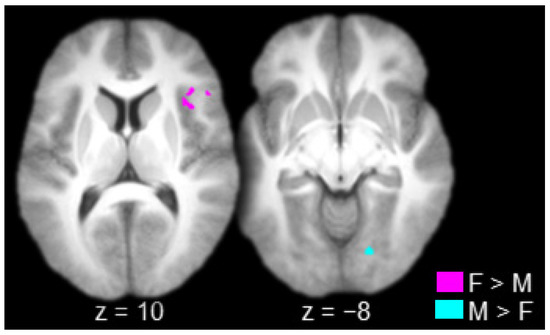

| Female (Hits > Misses) > Male (Hits > Misses) | |||||

| Positive activations | |||||

| R. Inferior Frontal Gyrus/Insula | 44/45 | 39 | 25 | 7 | 74 |

| Male (Hits > Misses) > Female (Hits > Misses) Negative activations | |||||

| L. Calcarine Sulcus/Lingual Gyrus | 17/18 | 19 | −76 | −5 | 32 |